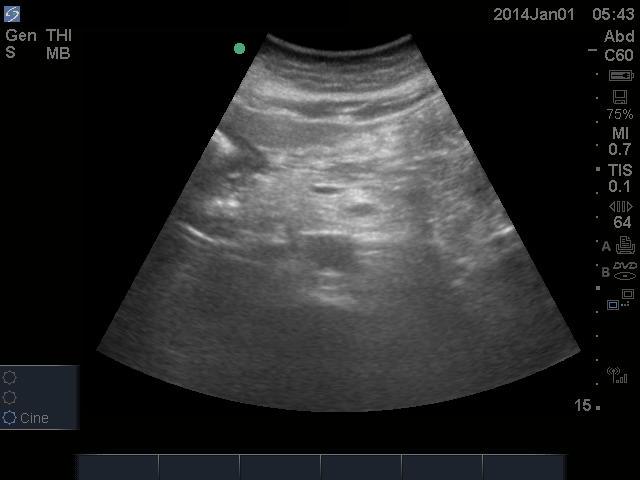

FAST showing no free fluid found here:

U/S aorta showing no AAA found here:

Pericardial U/S showing no effusion found here:

(All U/S images are courtesy of McMaster PoCUS Subspecialty Training Program)